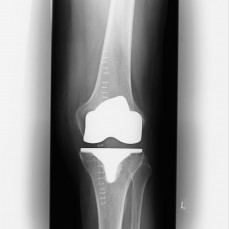

(Bilder unten: Totalendoprothese Kniegelenk)